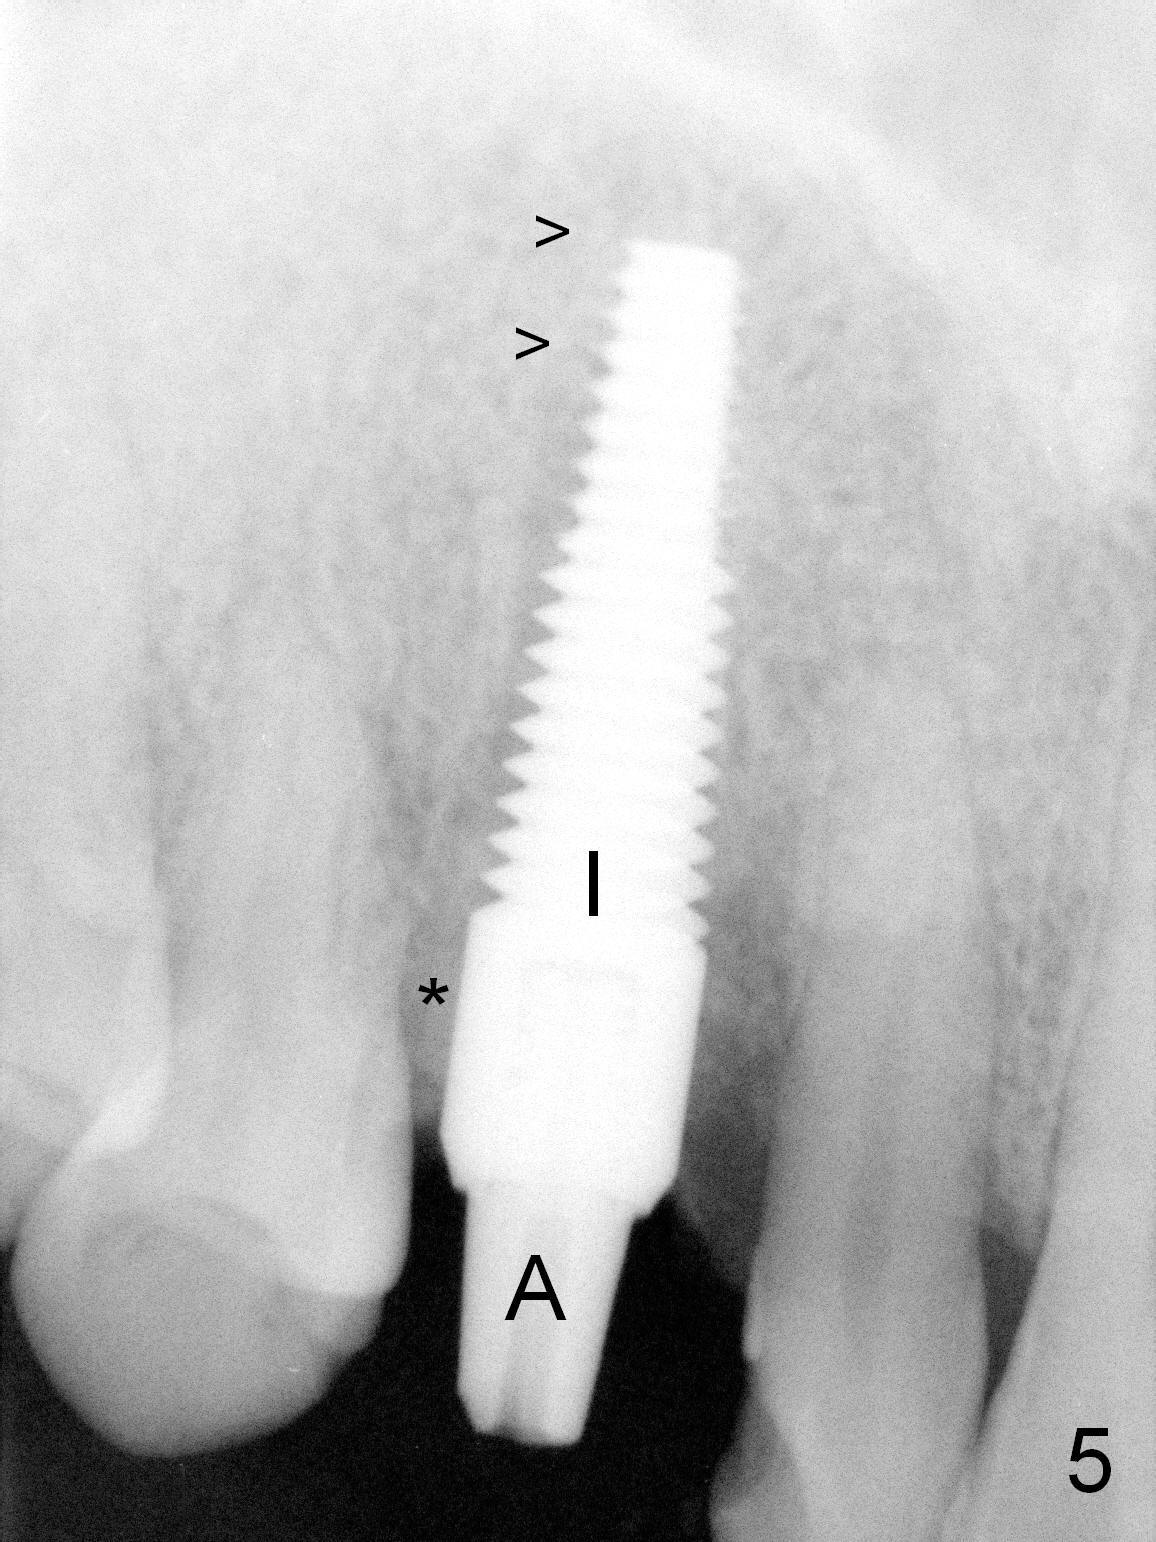

After 5x20 mm implant is placed, the distal gap is filled with bone graft (Fig.5 *). An abutment is placed (A) for fabrication of an immediate provisional (Fig.6 P). The latter hold the labial gingiva bulging (Fig.6 >). When the provisional is removed for bone grafting, the labial gingiva collapses (Fig.7 arrowheads). In fact a piece of cone-shaped Osteotape (Impladent) is placed palatal to the labial gingiva/thin labial plate and a small amount of graft is placed in the deepest area of the socket (labial to the osteotomy) prior to placement of the implant. More graft is placed in the peri-implant gap, particularly labially to keep the labial gingiva convex (Fig.8 arrowheads). The lacerated gingiva is to be approximated with perio glue (Fig.9 <). Collagen dressing is placed over the exposed graft before cementation of the provisional. Perio dressing is applied for further protection and seal.